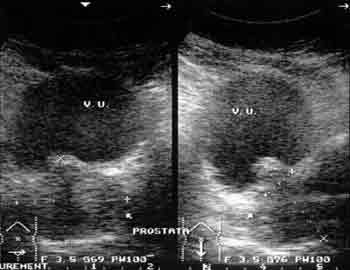

Ультразвуковая диагностика заболеваний предстательной железы.

Рис. 1. Аденоматозные узлы, оттесняющие стенку мочевого пузыря.